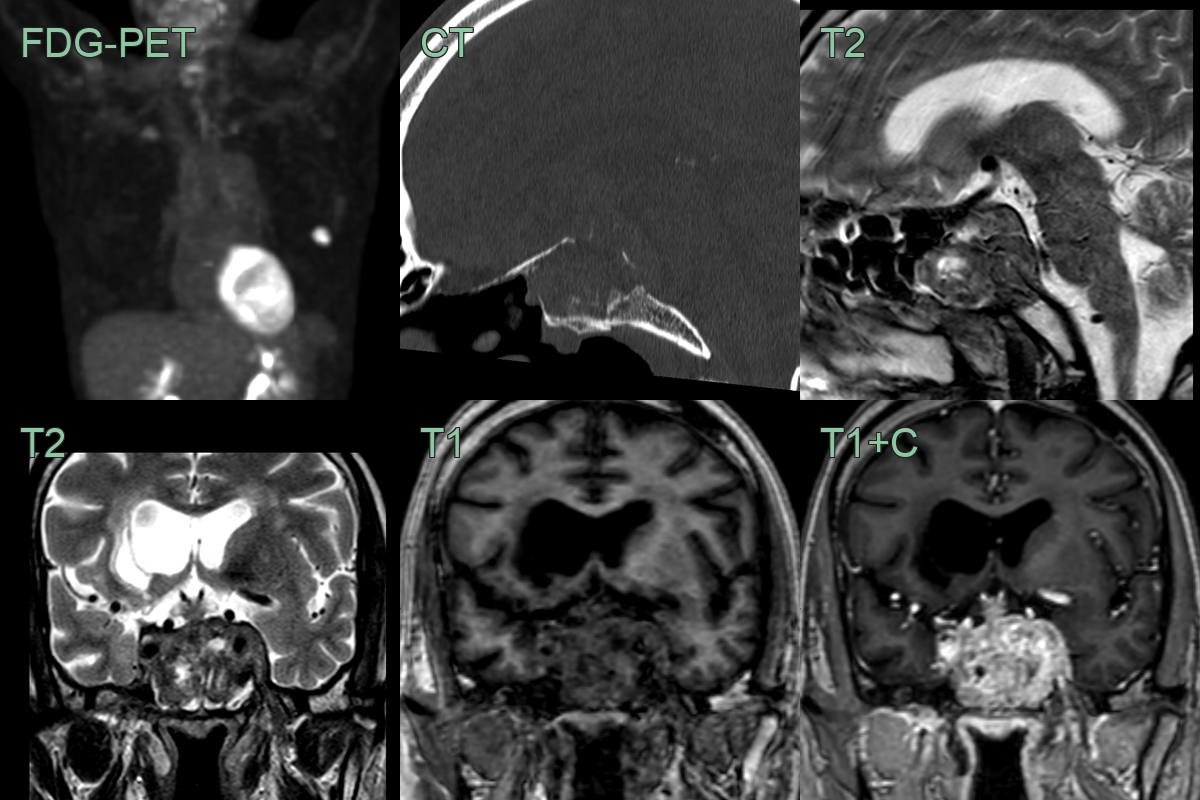

• A 60-year-old patient with a recent lung cancer diagnosis presented wiht headache and diplopia.

• CT showed a destructive lesion in the clivus and pitutiary fossa.

• MRI showed a heterogeneously enhancing lesion invading the left cavernous sinus.